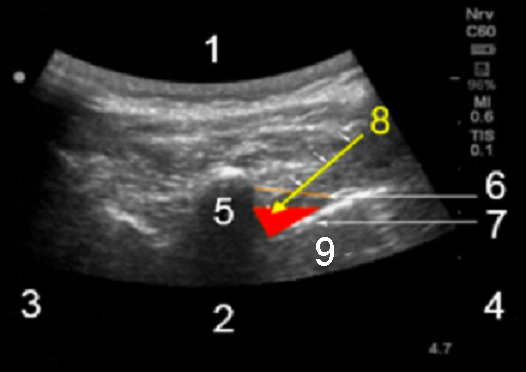

Paravertebral Sonoanatomy Image

1. Posterior

2. Anterior

3. Medial

4. Lateral

5. Transverse process

6. Internal intercostal membrane

7. Pleura

8. Yellow Arrow: Needle projection into PVS (red triangle)